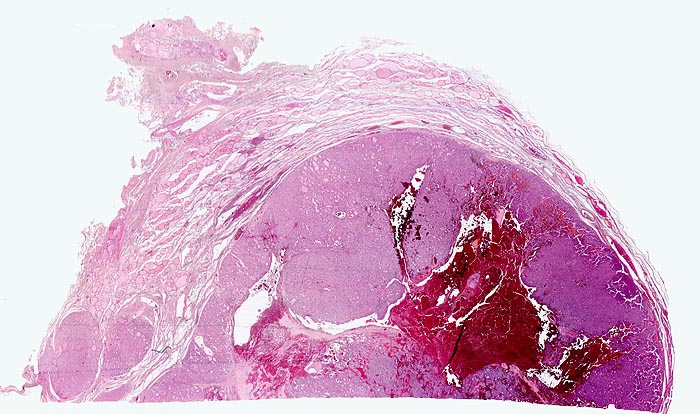

- Anschnitt eines grossen mikrofollikulären Knotens (autonomes Adenom) mit angedeuteter Kapsel und zentraler Einblutung. Oben zwei weitere kleine Satellitenknoten.

- Kompression des angrenzenden Schilddrüsenparenchyms. Dieses besteht aus grossen Follikeln mit kubischem oder abgeflachtem Epithel und reichlich kompaktem dunklem Kolloid in den Follikellumina.

- Zeichen gesteigerter hormoneller Aktivität im Adenom:

- Kleine Drüsenlumina.

- Teils mehrreihiges kubisches bis zylindrisches Epithel.

- Fehlendes oder nur spärliches helles Kolloid mit zahlreichen Resorptionsvakuolen.